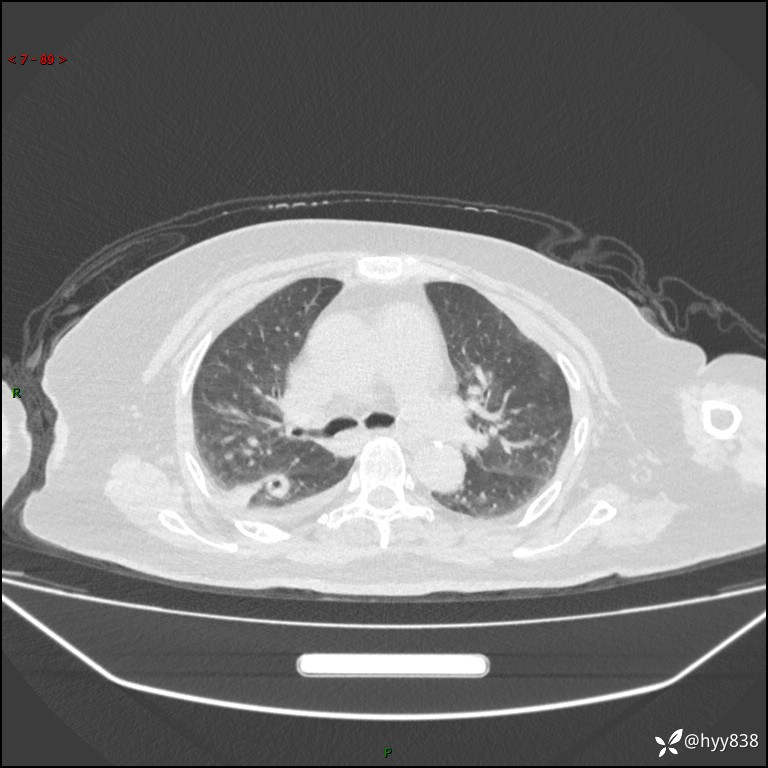

胸部 CT平扫、

颅脑MRI(T2WI+DWI)